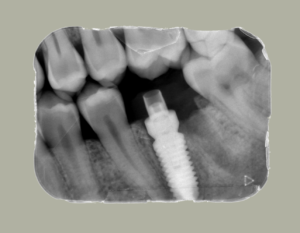

Antes de tomar una decisión, hay que realizar un buen estudio periodontal, hacer un periodontograma y ver el nivel de hueso residual que tiene el diente. Debemos, comprobar si el problema que tiene este diente sería a nivel restaurador, ver si se puede hacer una endodoncia, si se puede hacer una reconstrucción… e incluso, aunque necesitáramos realizar pequeño procedimiento quirúrgico, como un alargamiento coronario, la primera opción siente debe ser mantener ese diente natural.

Siempre tenemos que ver otros factores como la movilidad, la estética en el plan restaurador o dentro de la boca. Así como, la situación que tiene ese diente a la hora de masticar o su posición. Pero, siempre que podemos, la mejor opción será mantener los dientes naturales.